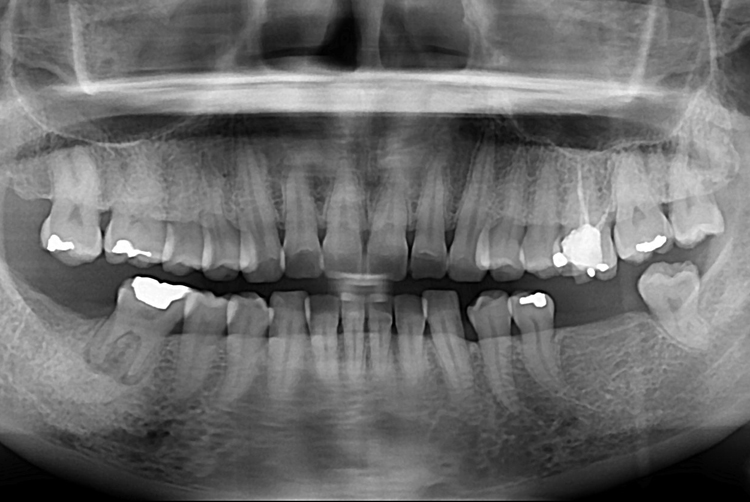

[임플란트] 어금니 임플란트

치료전 : 2017-10-17

세종치과는 많은 환자와 다양한 케이스를 바탕으로

항상 편안한 임플란트 수술을 제공하고자 노력하고,

오래동안 튼튼히 쓸 수 있는 임플란트 수술을 가장 큰 목표로 삼고 있습니다.